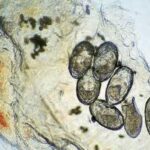

In the papulovesicular form of scabies, spongiosis is present in the stratum malpighii near the mite to such an extent that formation of a vesicle is often the result. Even if no mite is found in the sections, the presence of eggs containing larvae, of egg shells, or of fecal deposits (scyballa) within the stratum corneum is indicative of scabies . The dermal infiltrate in sections containing mites shows varying numbers of eosinophils. |

In Norwegian scabies, the thickened horny layer is riddled with innumerable mites, so that nearly every section shows several parasites . |